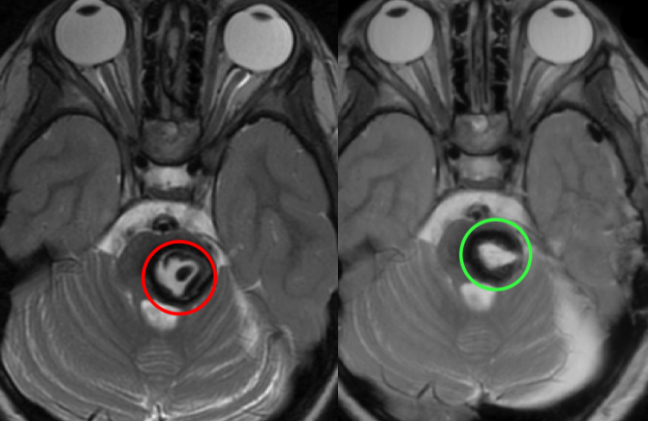

红色为术前,绿色为术后即时的颅脑MR,显示病变全切,无脑水肿、出血等,瘤腔内高信号灶是止血材料。